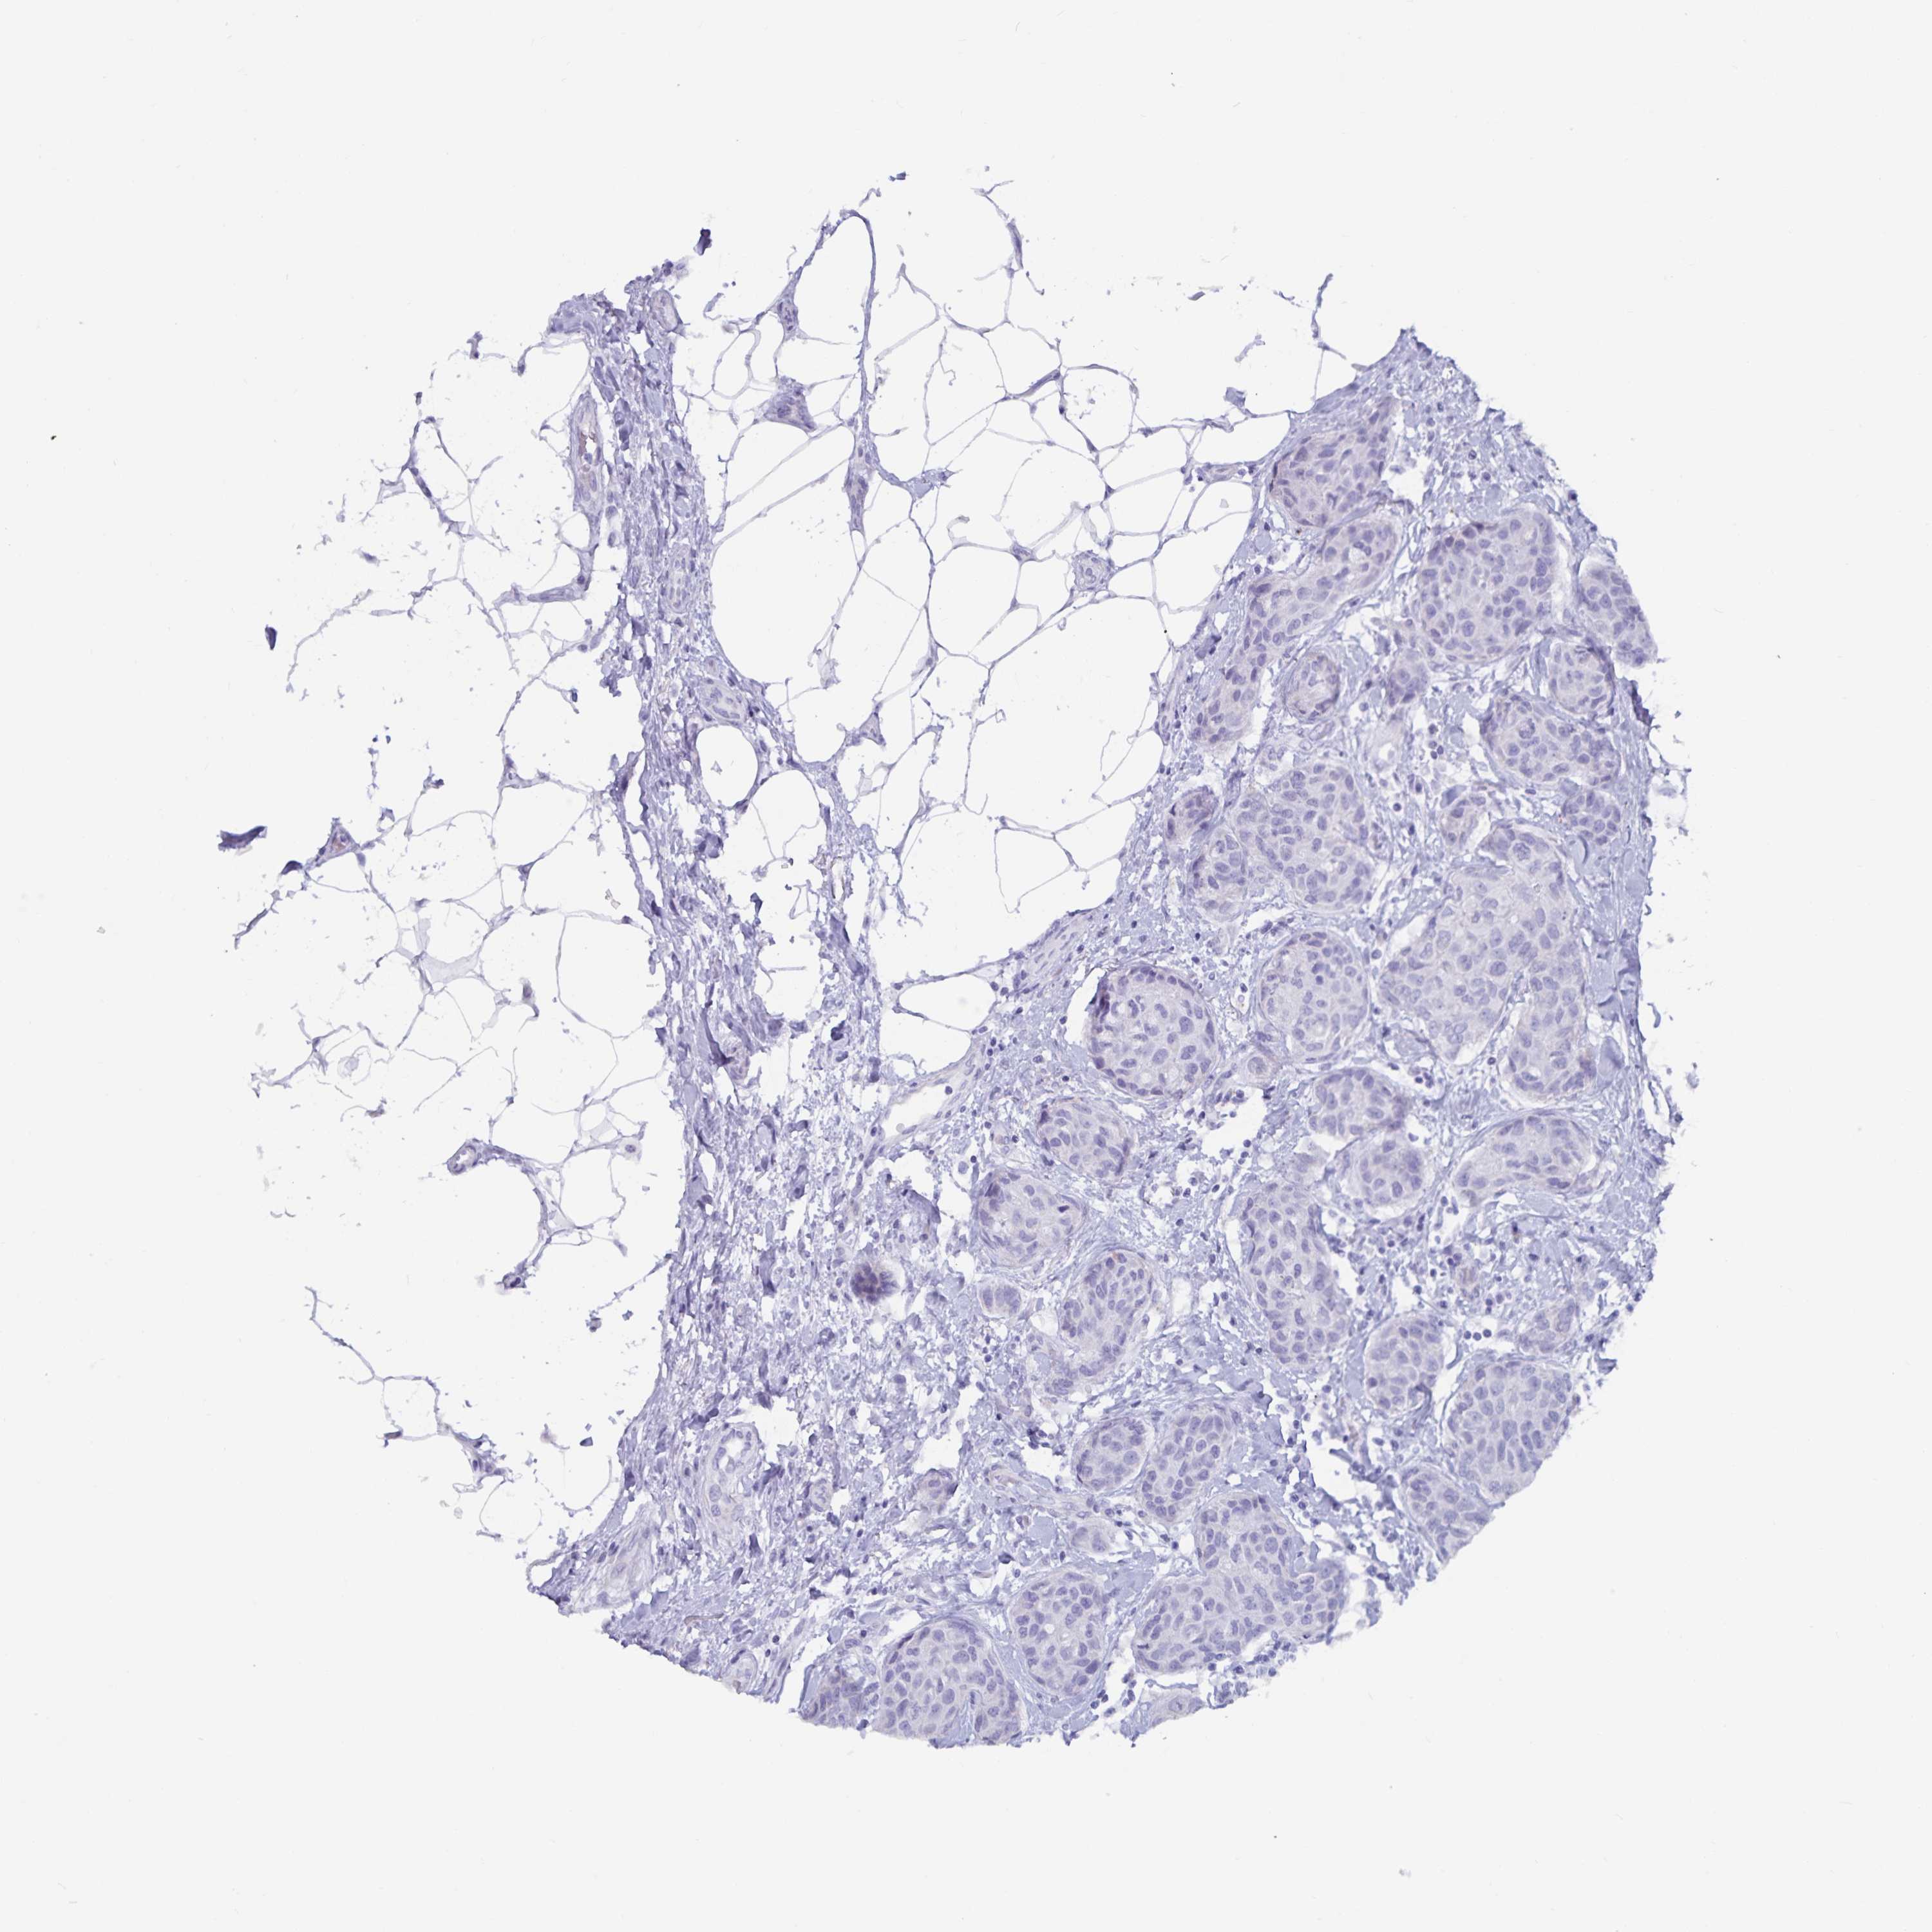

CANCER BREAST CANCER Show tissue menu

Breast cancer

Human cancer